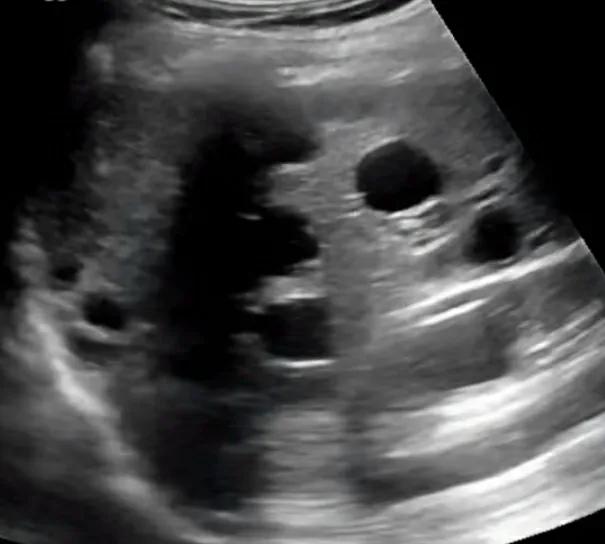

肝囊肿的诊断通常较简单, 普通的超声即可确诊 ,直径5mm左右即可被超声显示,典型的超声表现是,肝脏上显示的圆形或椭圆形无回声区 。

多囊肝